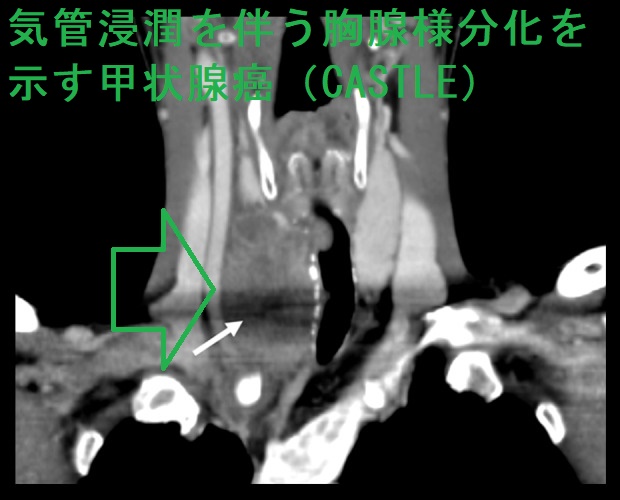

- 気管浸潤を伴うケースもある[Am J Case Rep. 2019 Dec 10;20:1845-1851.]

甲状腺の胸腺様分化を示す癌(CASTLE)の超音波(エコー)画像は、甲状腺悪性リンパ腫、甲状腺未分化癌、甲状腺原発扁平上皮癌と鑑別難で、辺縁不整・境界不明瞭、内部は不均一の低エコー結節(あるいは領域)。[Oncol Lett. 2016 Feb;11(2):1321-1326.]